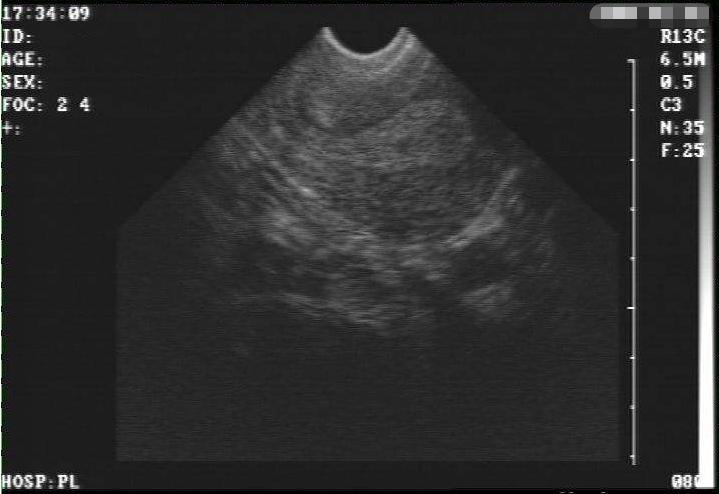

阴超检查是利用B超探头对阴道内进行观察,而腹式B超是对下腹部进行观察,但是由于卵巢的位置比较深,阴超检查会更加探查的更近一些。

阴超检查的结果会更加准确,即使是卵巢位置过深或是腹壁肥厚,也是阴超检查会更加适合,比起腹部B超,阴超会检查出更多的女性疾病。